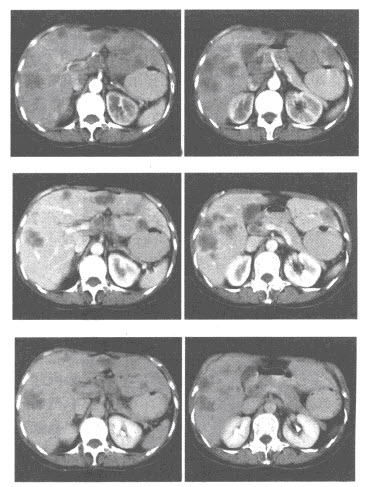

D.马蹄肾

154、单项选择题

男,52岁,贲门癌术后3年,肝脏CT增强扫描如图所示,考虑的疾病为()

A.贲门癌肝转移

B.原发性肝细胞癌

C.肝海绵状血管瘤

D.多囊肝

E.肝囊肿